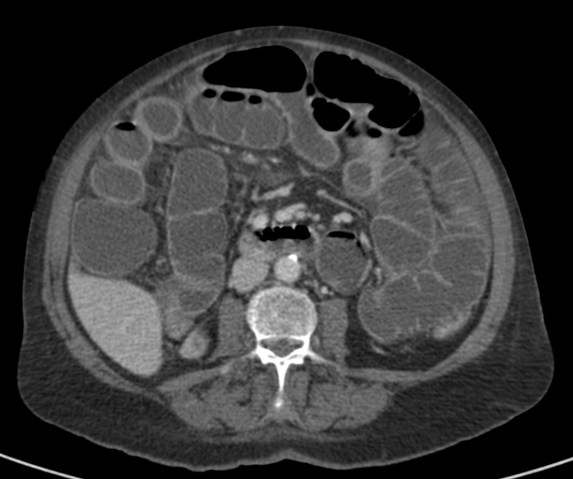

Se realiza TC de abdomen en vacío y con contraste en fase portal:

Estamos ante un cuadro de isquemia intestinal en un paciente con bajo gasto cardiaco con afectación principal de asas intestino delgado, territorio vacularizado por la arteria mesentérica superior.